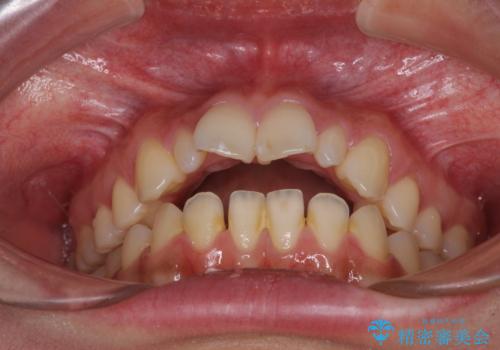

- 前方に飛び出した前歯を気にして来院された患者様です。

上下前歯同士の距離が離れているため、上顎左右第一小臼歯2本を抜歯することで前突を改善することとしました。

しかしながら、左右ともに側切歯が矮小歯であるため、矯正治療で矮小歯前後にスペースを作り、矯正治療後にオールセラミッククラウンにて補綴治療を行うこととしました。